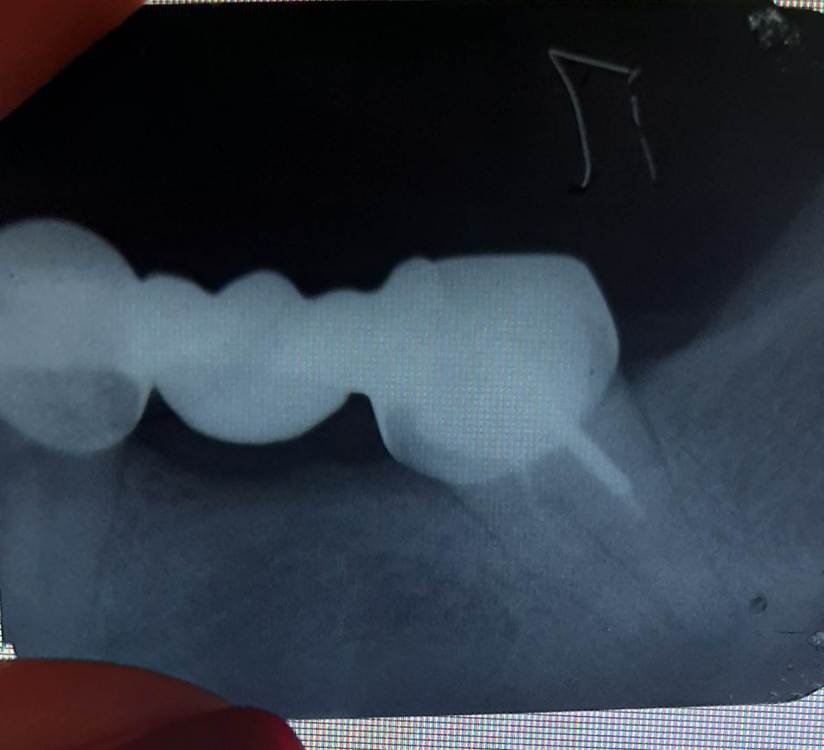

АннаКоала Опубликовано 29 января, 2024 Поделиться Опубликовано 29 января, 2024 Здравствуйте, мост стоит 7 лет. Последнее время иногда появляется ощущение под мостом, как будто там что застревает,внешне спокойная десна,почищу вроде проходит. На консультации два доктора говорят разное, один говорит менять мост,с обязательным перелечиванием каналов (7 зуб). Кстати микроскопа у него нет. А второй говорит, что в каналы лезть не надо, потому вариант удачи 50 на 50. Советует просто заменить мост. Пожалуйста выскажите свое мнение,перелечивать ли каналы перед протезированием? Ссылка на комментарий

Doc Опубликовано 29 января, 2024 Поделиться Опубликовано 29 января, 2024 Каналы однозначно не в порядке. Ссылка на комментарий

Carioznik Опубликовано 30 января, 2024 Поделиться Опубликовано 30 января, 2024 (изменено) 46 минут назад, АннаКоала сказал: Может тогда его не трогать вообще ? Ведь особо ничего не беспокоит. Можете не трогать, но когда начнет беспокоить, скорее всего, будет уже поздно, и придется точно удалять. Сейчас ещё есть шанс его сохранить (хотя, тоже вопрос: а есть ли смысл? Может зависеть от вариантов будущего перепротезировния) По этому снимку очень похоже, что на корне есть большое воспаление и кариес под коронкой. Изменено 30 января, 2024 пользователем Carioznik Ссылка на комментарий